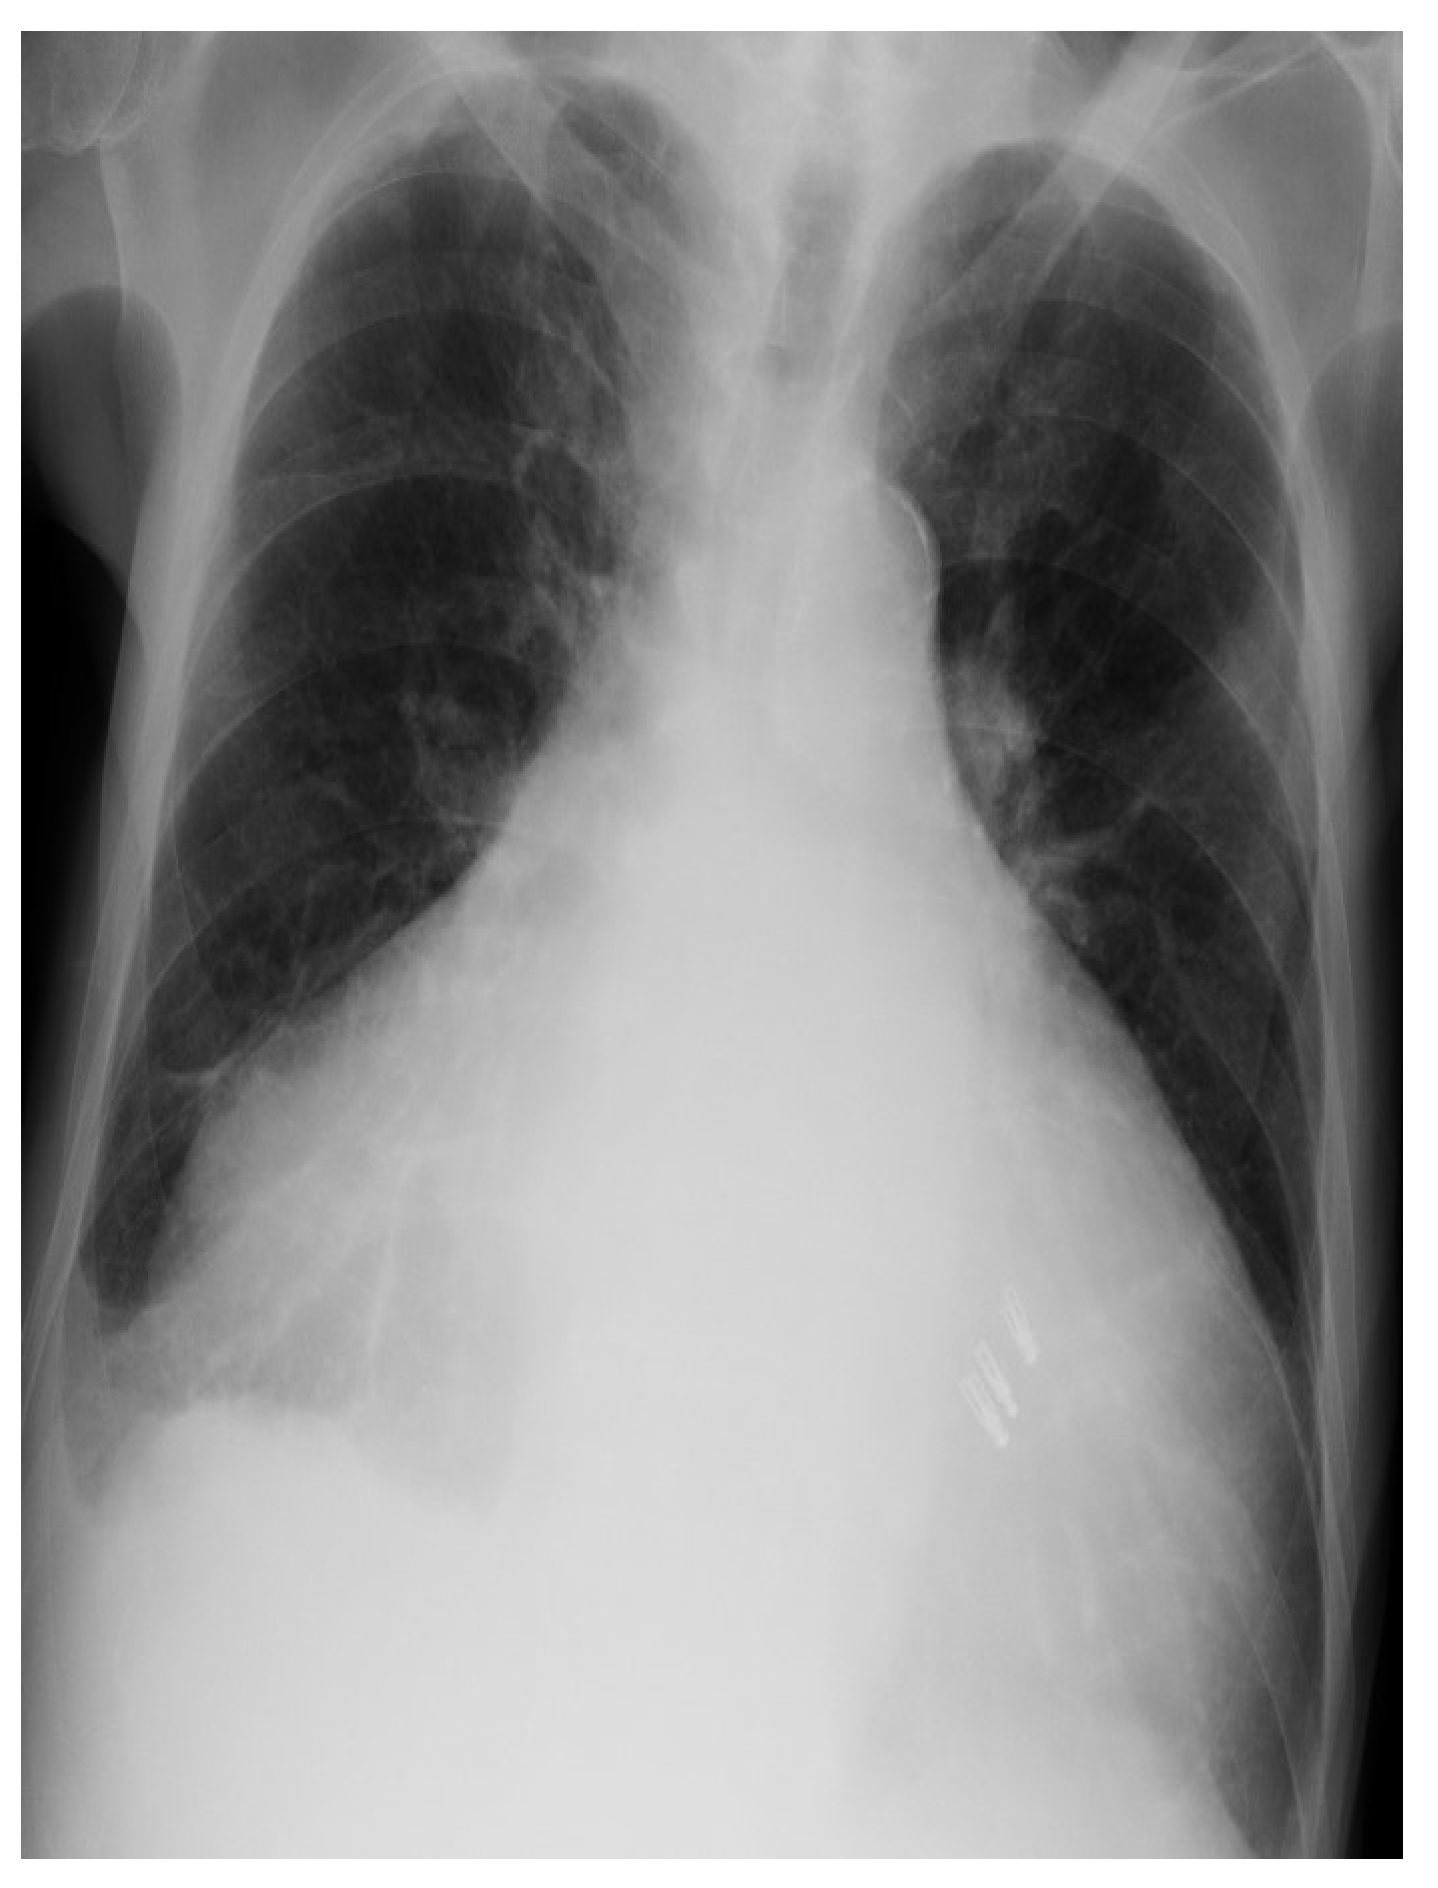

2. Case Presentation